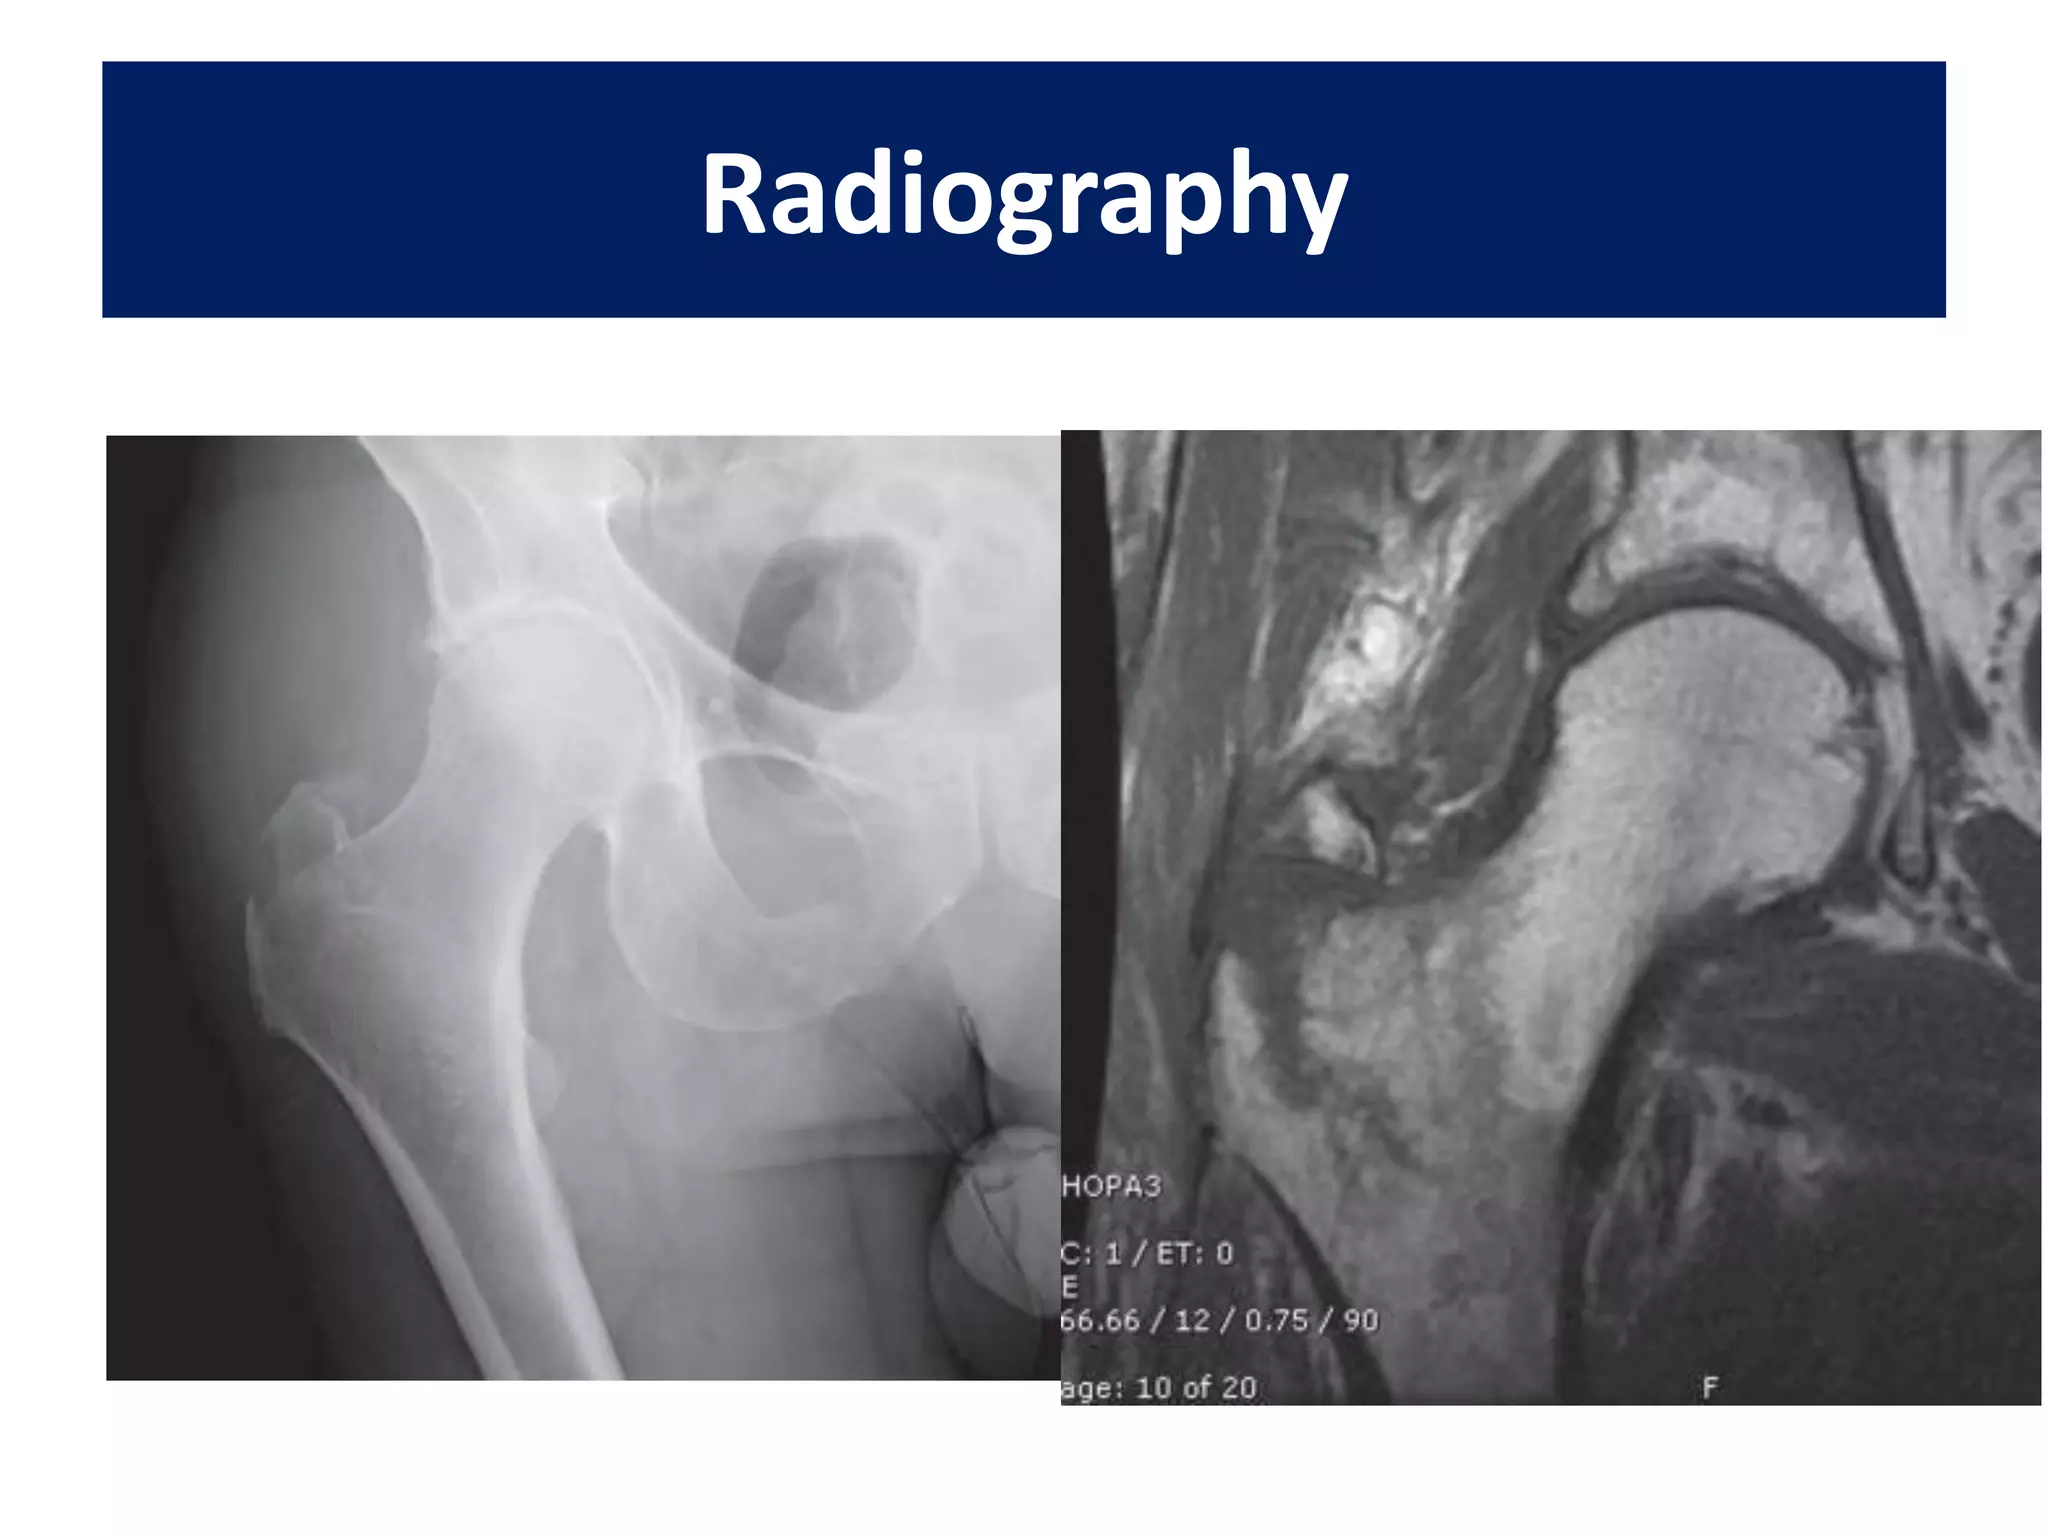

AAOS Guidelines

for preoperative practice

• Moderate evidence supports MRI as the

advanced imaging of choice for diagnosis of

presumed hip fracture not apparent on initial

radiographs.

• Due to the quality of existing literature, as well as potential

harm with radiation exposure related to use of CT in this

setting, this modality was not recommended for evaluation of

occult hip fracture